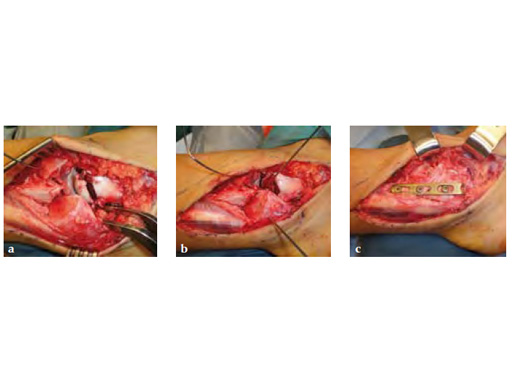

A 20-year-old construction worker fell from a 3 m height. He sustained a typical posterolateral impression and flake fracture of the talar dome.